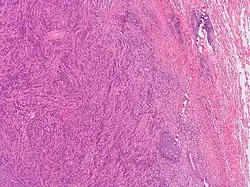

Histopathology

Analyzing the changes that arise in the tissue associated with the mass-forming lesion has been found to be the most accurate and precise method for confirming the diagnosis of plasma cell granulomas. This can be achieved by taking excision biopsies of the unknown mass for examination.[4] Typically, plasma cell granulomas appear microscopically as a lesional mass consisting of an abundance of plasma cells intermingled among different inflammatory cells set in fibrous connective tissue displayed in a spiral appearance.[3][4] Depending on the location of the plasma cell granuloma, vasculitis can be present but is not considered a confirmatory factor for diagnosis.[3] Kappa/lambda in-situ hybridization is another diagnostic test that needs to be done when trying to characterize the lesion for further confirmation.[3] Common results associated with kappa/lambda in-situ hybridization studies of PCGs are an abundant population of CD138 positive polyclonal plasma cells.[3] If instead, results show monoclonality of plasma cells it is indicative of plasmacytoma.[3]